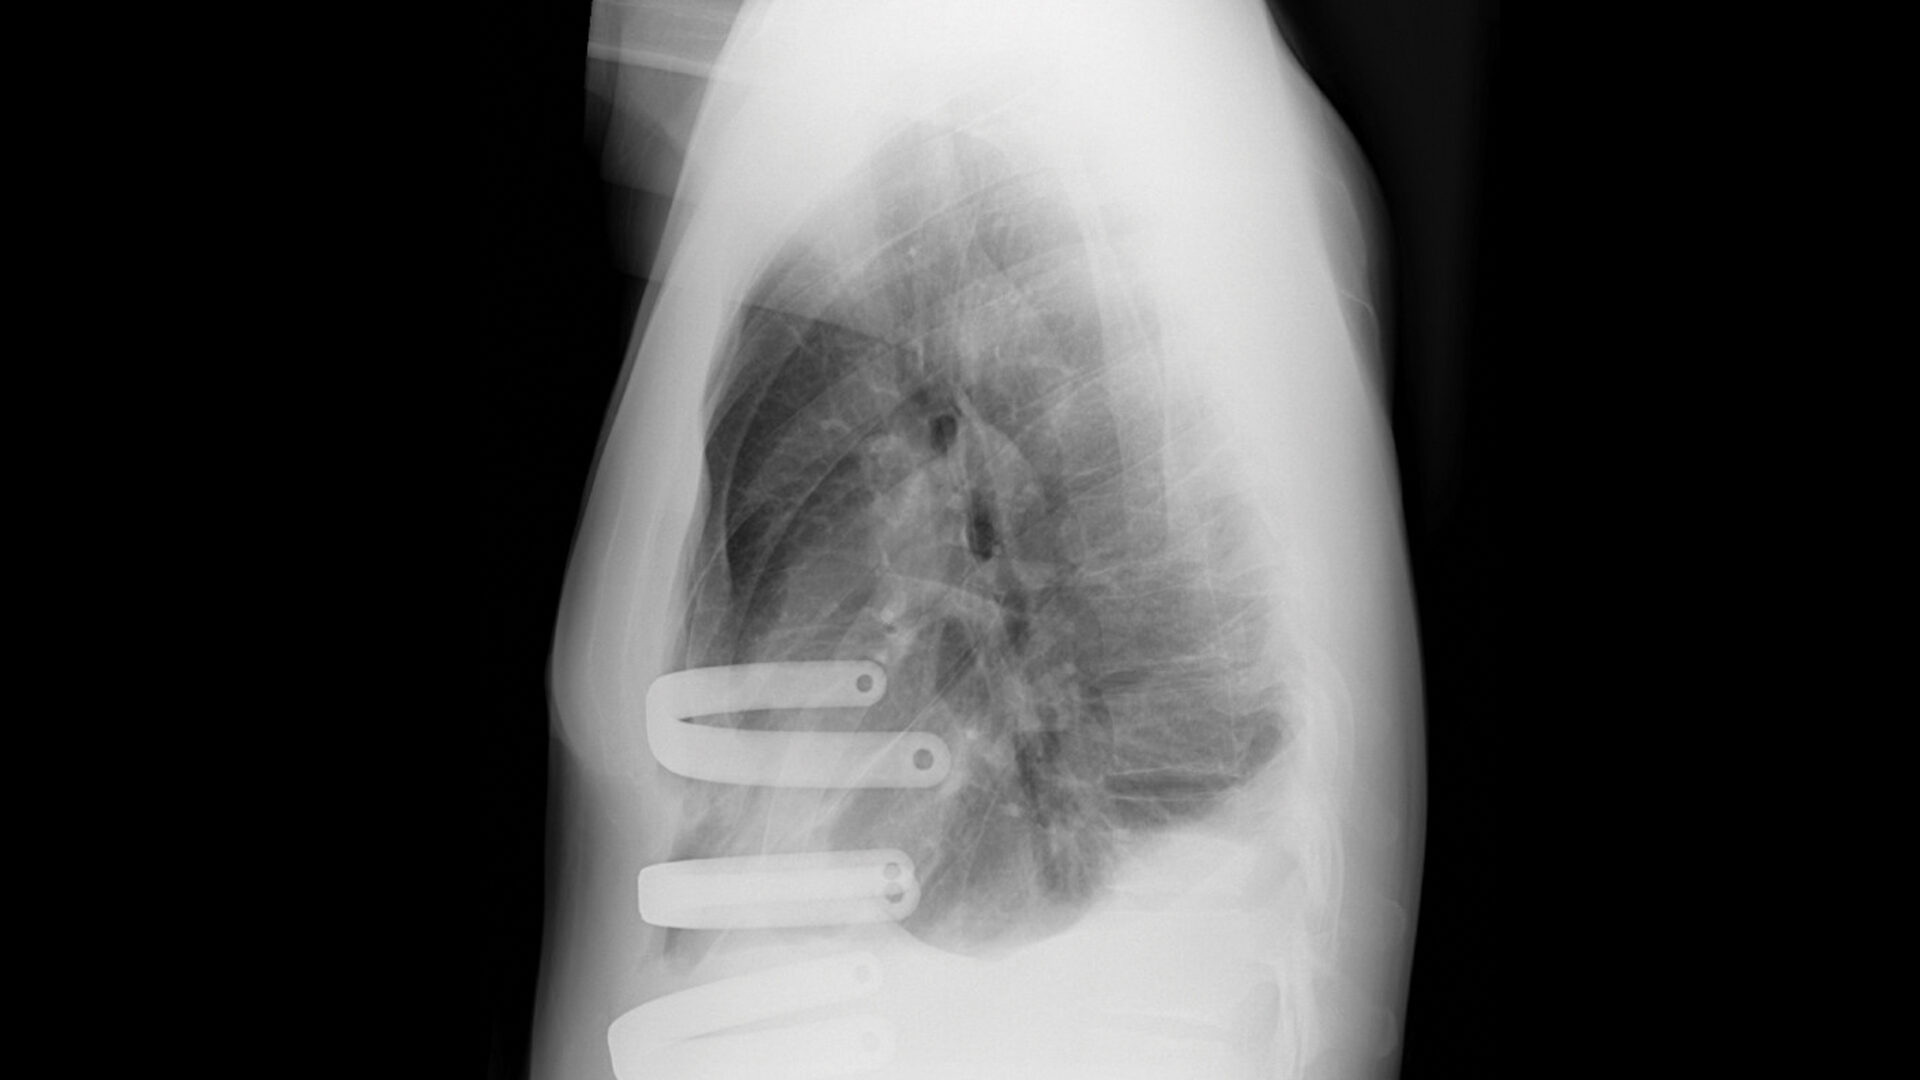

Under thoracoscopic guidance, Dr. Bizekis performed the Nuss procedure via two bilateral, 3-centimeter lateral chest wall incisions. After freeing up tissue under the sternum with a handheld sound incision device, he inserted three U-shaped, malleable titanium bars using passers connected to a guiding rod, conforming the bars to the chest wall.

“We decide intraoperatively how many bars to use. Although one or two bars is common, we implanted three bars because of the severity of this case,” Dr. Bizekis says.

During the operation, the bars were positioned one interspace apart in a submuscular plane along the outer surface of the pectoralis muscle and inverted to remodel the anterior chest wall, achieving correction without tissue resection, dissection, or chest tube drainage. The bars were secured to the lateral chest wall with FiberWire sutures.

Postoperative X-ray showing placement of the three U-shaped titanium bars. Source: NYU Langone Health